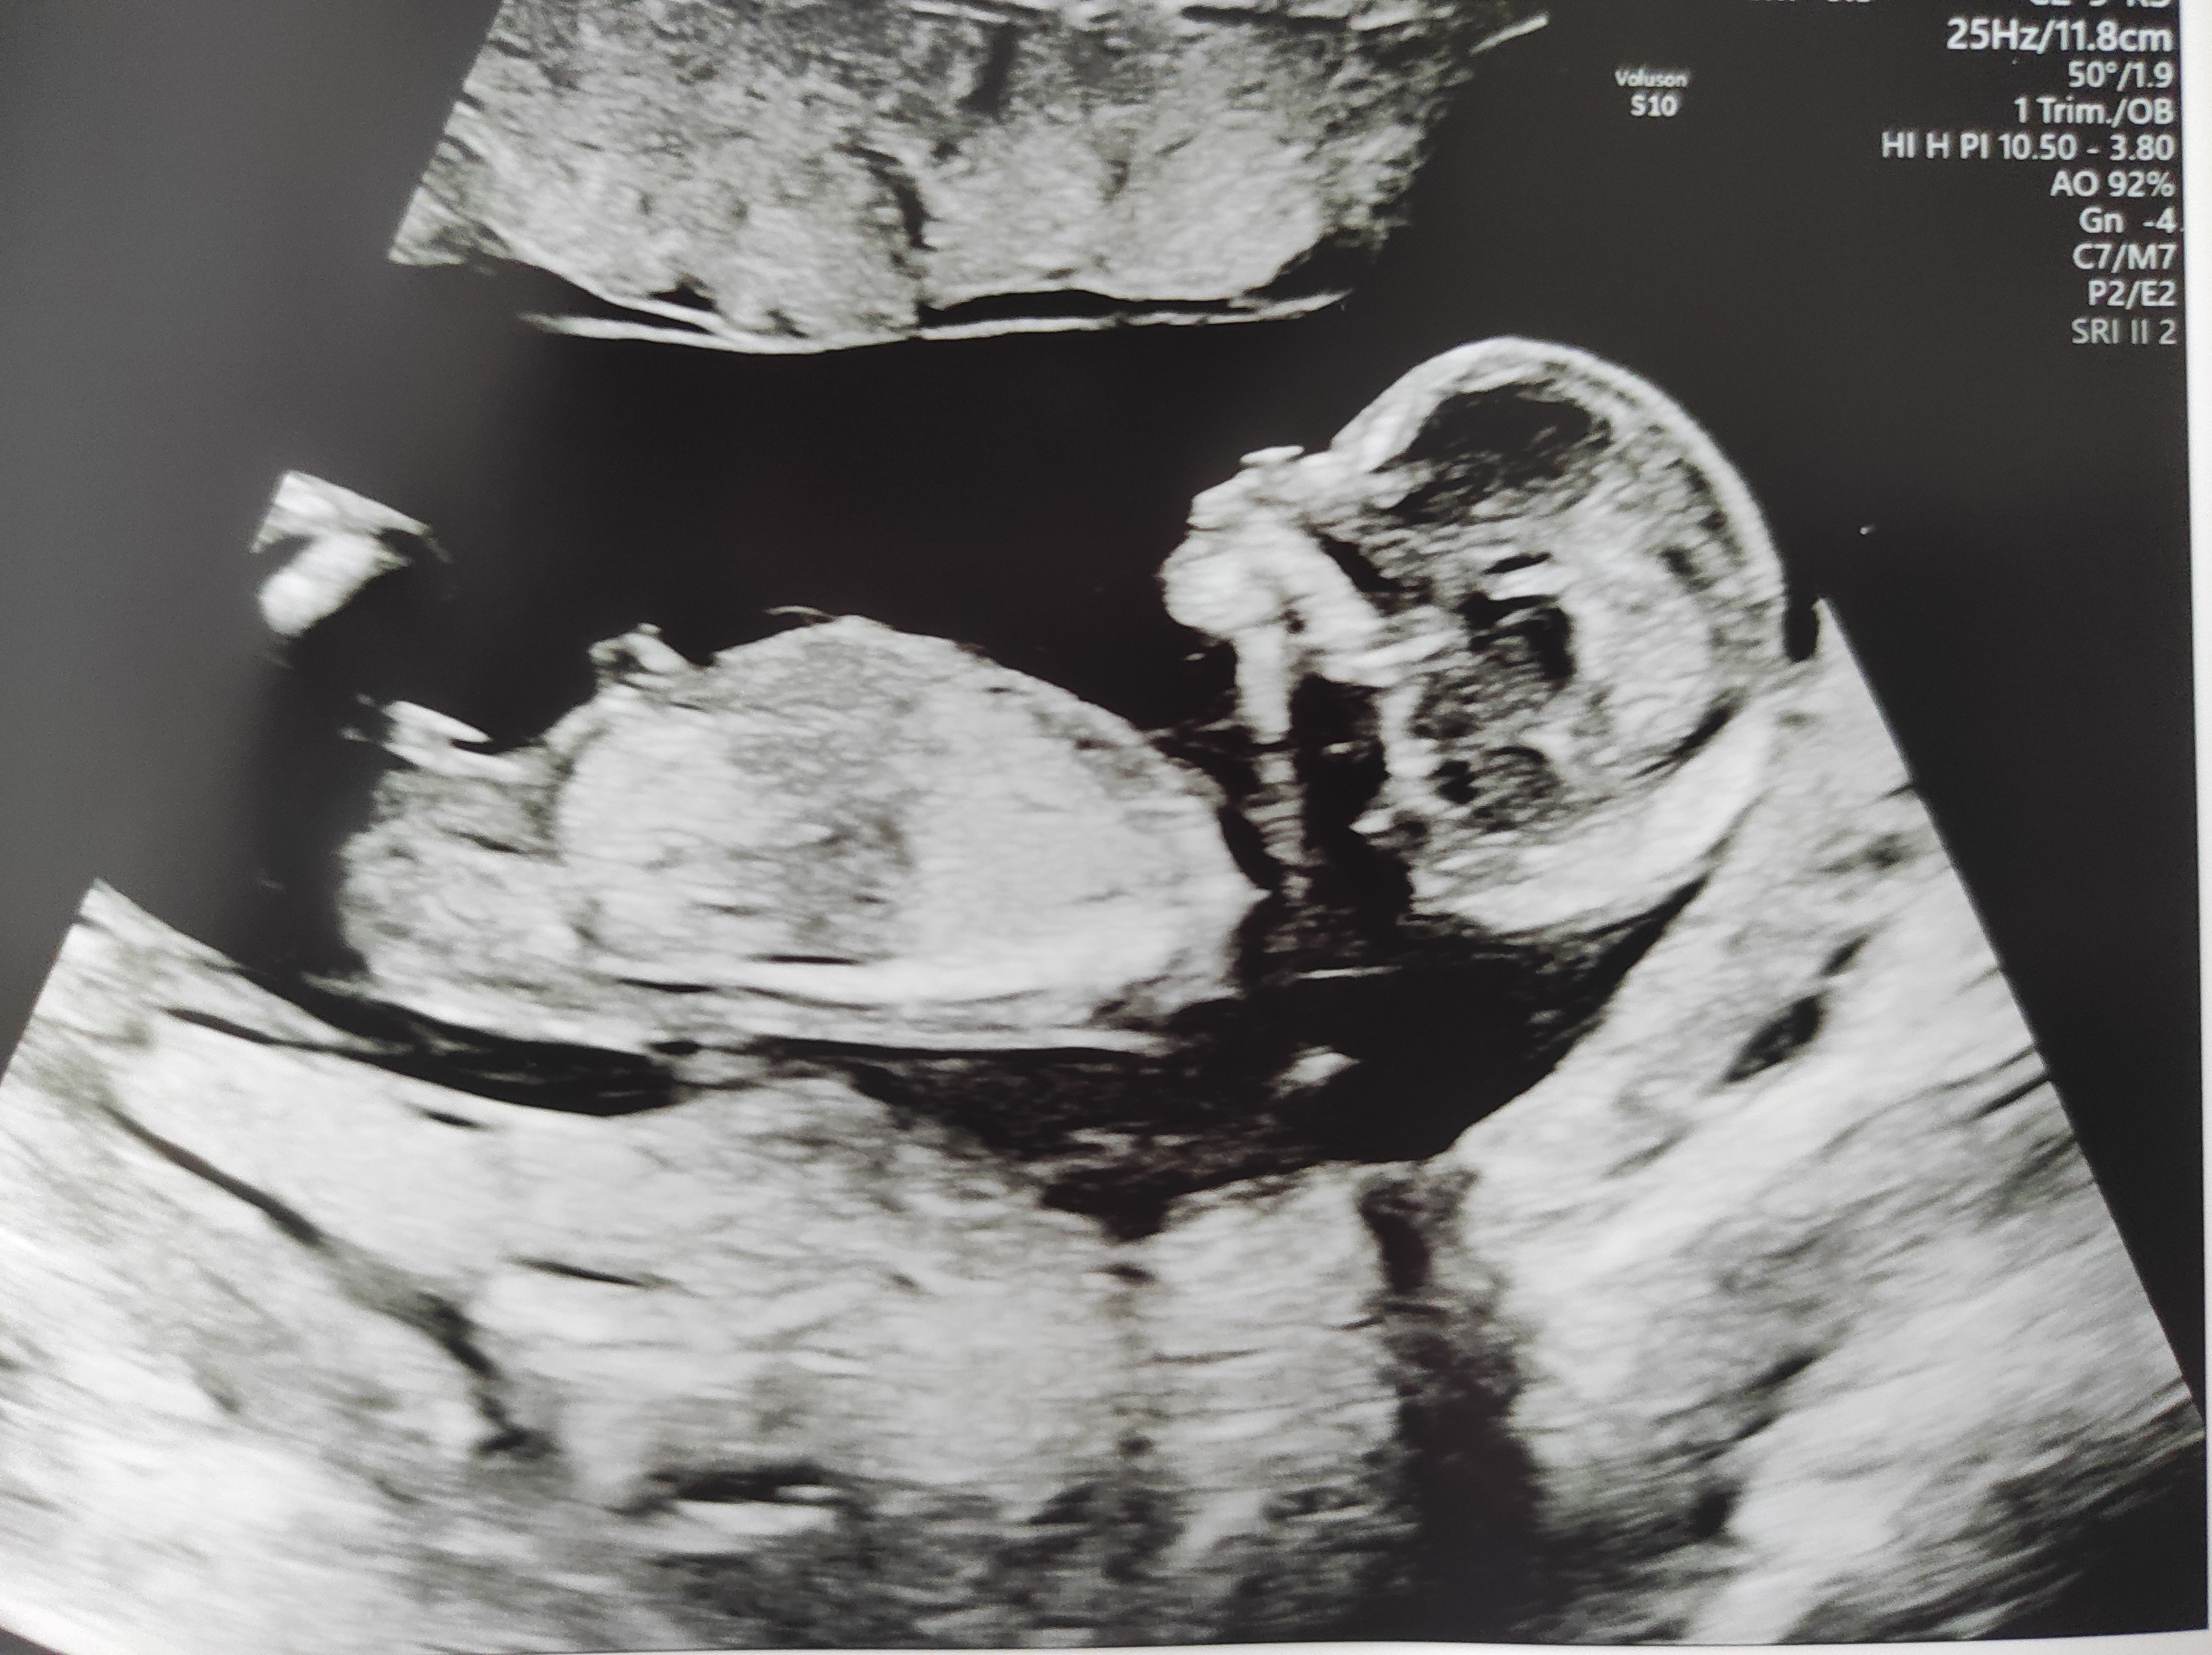

Nub-teoria

Näkyykö tässä?:)

Noissa alemmissa ei näy mitään, mutta kyllä mä nyt sanoisin että poika. Nub on selkeä kyllä, mutta mua jännittää arvioida koska en tiedä jatkuuko se vielä tosta vai oisko koko nub nyt sit tossa kuvassa. 😁